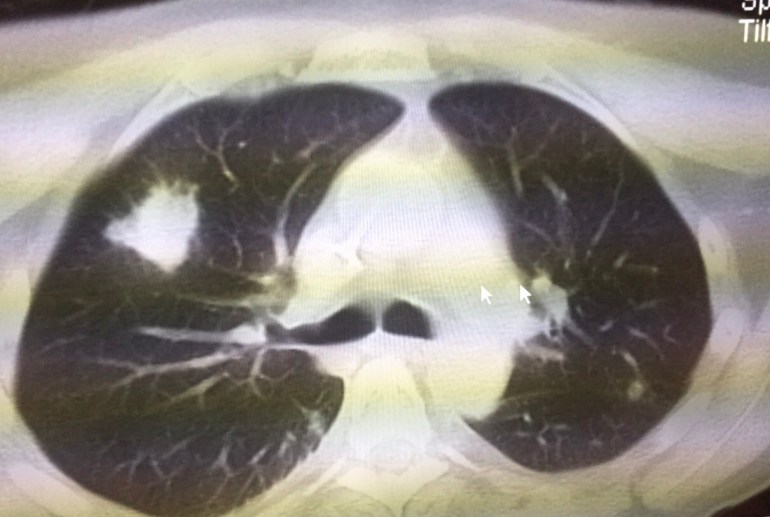

Just after engraftment, he developed fever again (absolute neutrophil count of 370 cells/cubic millimetre of blood). Septic work up was negative, and empirical piperacillin/tazobactam for 5 days did not help. A CT thorax was done, showing a solid nodule (figure). He had remained on oral posaconazole throughout the period.